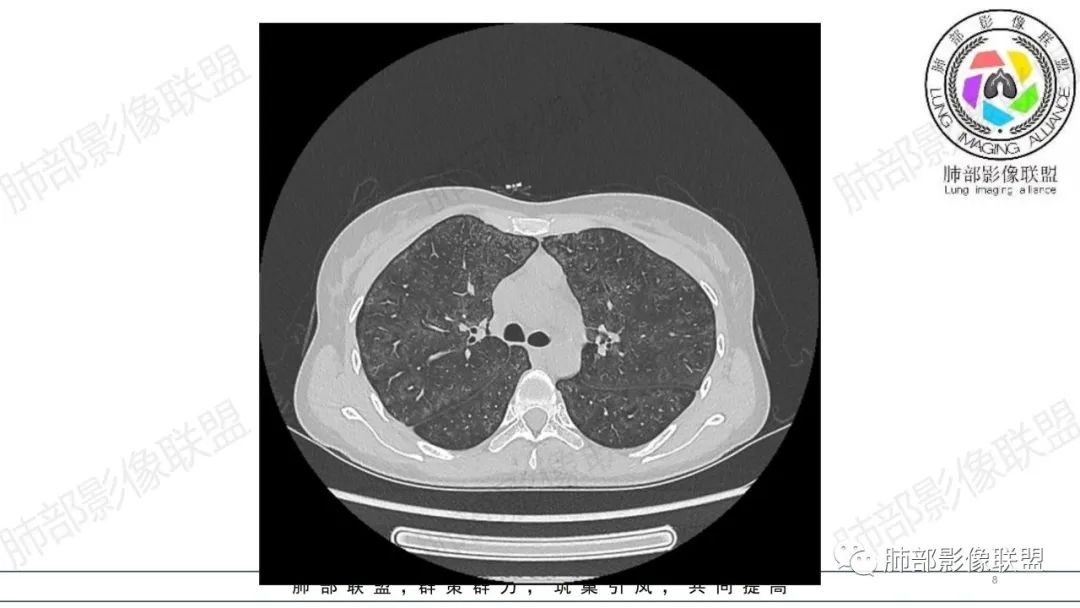

影像资料

34岁女性患者,“哮喘”病史30年,近期有可疑刺激性气体吸入史;因乏力半年,咳嗽、憋气、发热4天就诊;6.1CT提示双肺广泛毛玻璃影及粟粒样结节,胸膜下闲置及血管周闲置,可见树丫征,部分小叶间隔增厚。考虑:1.过敏性肺泡炎,有可疑刺激气体接触史,胸膜下闲置,广泛毛玻璃影,地图样分布,粟粒结节边界模糊,支持过敏性肺泡炎,但糖皮激素治疗效果不佳,且动态复查血常规血红蛋白进行性降低,过敏性肺泡炎 不符合;2.肺含铁血黄素沉积症:患者30“哮喘”病史,可能为肺含铁症状,肺部CT提示双肺弥漫毛玻璃影及粟粒结节影,中下肺明显,肺底部分小叶间隔增厚,近期咳嗽、憋气、发热,血常规血红蛋白进行性下降,考虑肺含铁急性期症状,但临床无咯血症状,肺含铁不典型。综合考虑:肺含铁血黄素沉积症>过敏性肺泡炎。

年轻女性 ,急性喘息发热,肺部影像弥漫磨玻璃密度,部分细小腺泡结节,胸膜下黑线显示,短期复查,病变密度增高,下肺明显,血管周围肺组织累及较少、且逐渐成小叶间隔分布。考虑弥漫肺泡内病变,并经淋巴道转移,下肺比上肺明显,多为免疫细胞功能下肺较强。1.过敏性肺泡炎,有相关病史,三层密度特点、头尾测分布,符合。2 肺泡微石症,多有钙化,且缓慢起病,病程不太符合,放待排。3 吸入相关肺损伤,有病史,疾病演变过程也符合渗出-肉芽肿改变,建议详细询问病史。4 感染性病变,结核?病变气道分布为主,如此弥漫且没有树丫不符合。5.巨细胞病毒,可以磨玻璃 结节 改变,没有免疫缺陷病史。最后考虑吸入所致 1过敏性肺泡炎、吸入性肺损伤 鉴别肺泡微石症。

肺内气腔磨玻璃结节,肝脾肿大,治疗后间质改变,弥漫大B可能